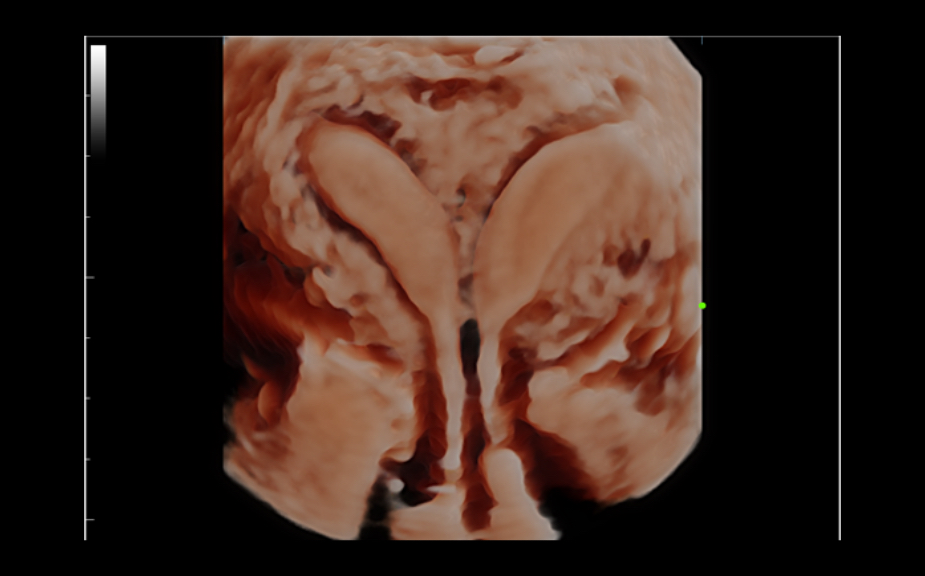

DC-80A con X-Insight mette a disposizione strumenti di una intelligenza eccezionale specifici per la cura della donna, dalla fertilit├Ā allo screening prenatale, e al post partum.

Immagini cliniche